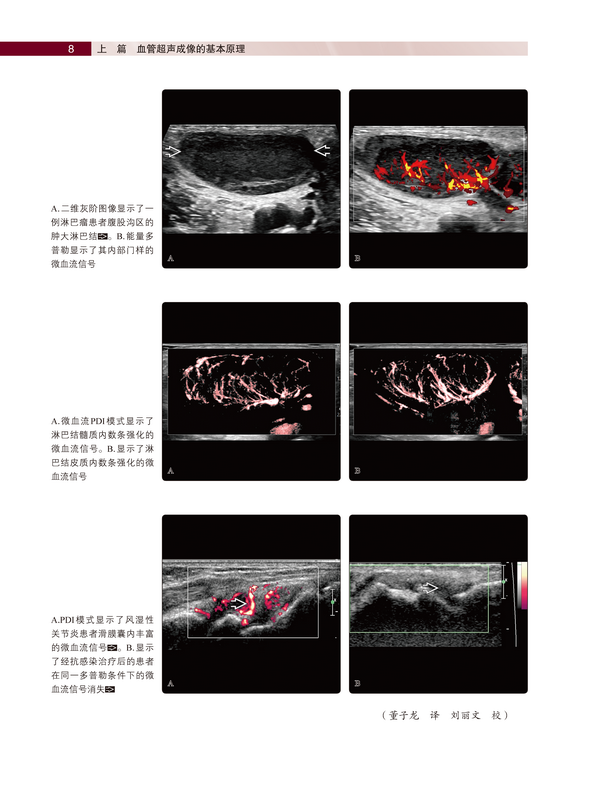

《血管超声诊断》阐述了血管超声成像的基本原理(包括彩色多普勒、能量多普勒、频谱多普勒、超声造影、微血流成像等技术);介绍了血管超声解剖基础,包括头颈部、胸部、腹部和四肢血管正常解剖及超声切面讲解、正常血管超声表现、影像成像优缺点分析;详细介绍了超声技术在血管疾病中的应用,包括血管介入治疗术前超声评估,手术流程标准化、规范化操作,术后并发症的诊断及超声表现等。《血管超声诊断》的一大特色是对每一章节内容均进行了简要总结列在文前,此外,小标题和亚标题的使用令阅读和查询更加便捷,方便读者能够迅速、准确地获取知识点。正文按照大体解剖学、影像解剖学、成像建议(部分章节涉及胚胎学)进行详细介绍。《血管超声诊断》的另一特色是每章节之后都配有丰富翔实、高清晰度的解剖及影像学彩色图谱,对脏器血管全方位、立体化展示,帮助初学者快速掌握血管正常结构及常见疾病的超声表现。